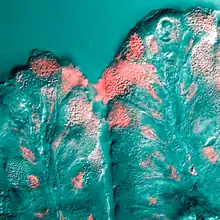

In the human respiratory system, mucus is part of the airway surface liquid (ASL), also known as epithelial lining fluid (ELF), that lines most of the respiratory tract. The airway surface liquid consists of a sol layer termed the periciliary liquid layer and an overlying gel layer termed the mucus layer. The periciliary liquid layer is so named as it surrounds the cilia and lies on top of the surface epithelium.[4][5][6] The periciliary liquid layer surrounding the cilia consists of a gel meshwork of cell-tethered mucins and polysaccharides.[7] The mucus blanket aids in the protection of the lungs by trapping foreign particles before they can enter them, in particular through the nose during normal breathing.[8]

In the airways—the trachea, bronchi, and bronchioles—the lining of mucus is produced by specialized airway epithelial cells called goblet cells, and submucosal glands. Small particles such as dust, particulate pollutants, and allergens, as well as infectious agents and bacteria are caught in the viscous nasal or airway mucus and prevented from entering the system. This process, together with the continual movement of the cilia on the respiratory epithelium toward the oropharynx (mucociliary clearance), helps prevent foreign objects from entering the lungs during breathing. This explains why coughing often occurs in those who smoke cigarettes. The body's natural reaction is to increase mucus production. In addition, mucus aids in moisturizing the inhaled air and prevents tissues such as the nasal and airway epithelia from drying out.[11]